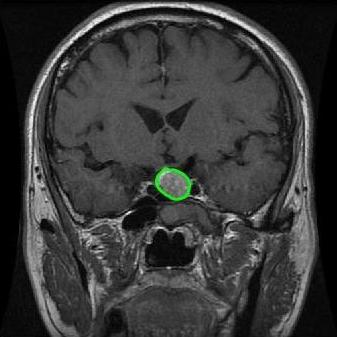

From the above discussions, we have discovered the significant potential of applying Retinex theory to image segmentation and explored its fundamental differences from traditional models. Traditional image segmentation models typically focus on the impact of intensity information on the segmentation results. Therefore, when faced with complex segmentation scenarios, the segmentation results are often affected by lighting, artifacts, and unclear boundaries in the image. As shown in Fig. 1, we present the results of the classical local model LIF [ZHANG20101199] for segmenting brain tumor images along with surrounding tissue edema. The irregular ring-like enhancement caused by the edematous tissue leads to irregular boundaries and low contrast in the images. Consequently, the LIF model can only identify the central necrotic and liquefied regions of the tumor, failing to detect the boundaries and becoming trapped in local minima. In this paper, we draw inspiration from the Retinex theory, which is widely applied in the field of image enhancement. According to Retinex theory, the reflectance component characterizes the intrinsic structural properties of the observed image and preserves texture information independent of illumination variations. By integrating this reflectance component into the level set framework, our model achieves robust segmentation of medical images even under severe intensity inhomogeneity. In addition, a linearized Structural-Prior is proposed to restore intensity consistency and capture local geometric features, thereby improving boundary localization in complex or blurred regions. Furthermore, a relaxed binary level set representation is employed to enhance robustness against noise and to enable accurate tracking of complex contours. Based on these innovations, we propose a novel variational reflectance-based level set model (RefLSM) that simultaneously corrects bias fields and performs segmentation. Experimental results demonstrate that RefLSM significantly outperforms conventional level set methods in both segmentation accuracy and robustness. We present the results of our model segmenting the two brain tumor images mentioned above in Fig. 2.

To address the challenge of segmenting images with severe intensity inhomogeneity, we propose a linearized structural prior that directly operates on the reflectance component . Reflectance-based structural information is more robust to illumination variations and bias field distortions, helping preserve weak edges and subtle anatomical boundaries. As shown in Fig. 2, our method can accurately delineate tumor boundaries and surrounding edema even under severe inhomogeneity, where traditional intensity-based models often fail. The proposed prior aligns smoothed reflectance gradients with data-driven directions, enhancing inter-region contrast, preserving weak edges, and stabilizing the evolution of . Formally, we define the linear structure operator as the gradient field of the smoothed reflectance: